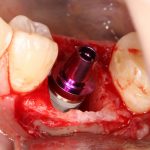

Для решения поставленной клинической задачи мы выбрали имплантационную систему Xive. Из имеющихся у нас трёх имплантационных систем, она лучше всего подходит для немедленной имплантации и немедленной нагрузки, и вот, почему:

Теоретически, для данной работы мы можем использовать абсолютно любую имплантационную систему, но с Xive это сделать проще. Тем более, что в клинике мы держим склад из более, чем трехсот имплантатов и компонентов, поэтому не переживаем по поводу того, что к моменту операции чего-то не будет в наличии. У нас всё всегда есть.

В процессе ирригации лунки промываются, что позволило нам еще раз подтвердить ранее сделанные выводы. С помощью аналогов имплантатов, входящих в хирургический набор Xive, мы проверили возможность стабилизации имплантатов в будущих лунках. Исходя из правил подбора и позиционирования имплантатов (я очень рекомендую почитать об этом здесь>>) мы остановились на Xive S диаметром 3,4 мм и длиной 13 мм.

По ряду уже упомянутых выше причин, для решения этой клинической задачи мы выбрали имплантаты Xive. Лунки для них мы уже приготовили. возможную первичную стабильность оценили. Имплантаты мы установили с усилием чуть больше 15-20 Нсм — такого крутящего момента более, чем достаточно, особенно если учесть, что временные коронки будут соединяться между собой.